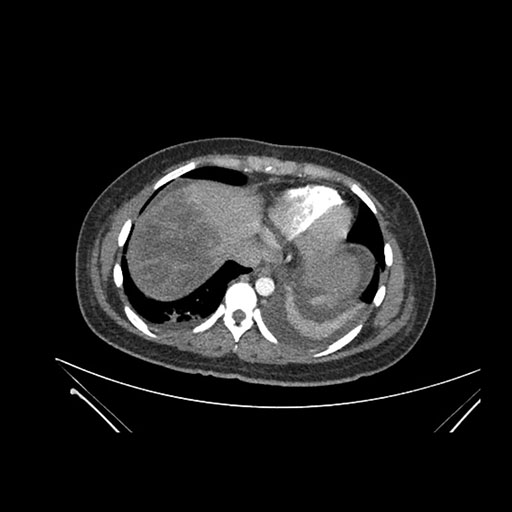

Axial Venous